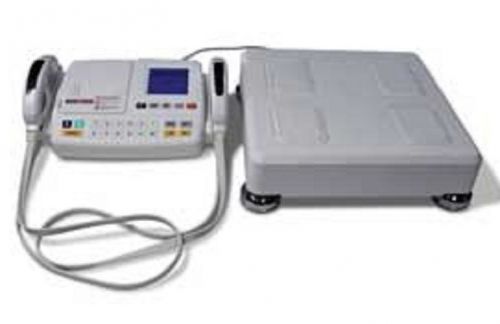

MedGraphics 7000 Cardiorespiratory Diagnostic Systems Spirometer Lung Function

Collins IPL 4400 Pulmonary Lung Function Tester with Warranty

Sensormedics VMAX Software Kit Max Pressure Option 770233E 770258